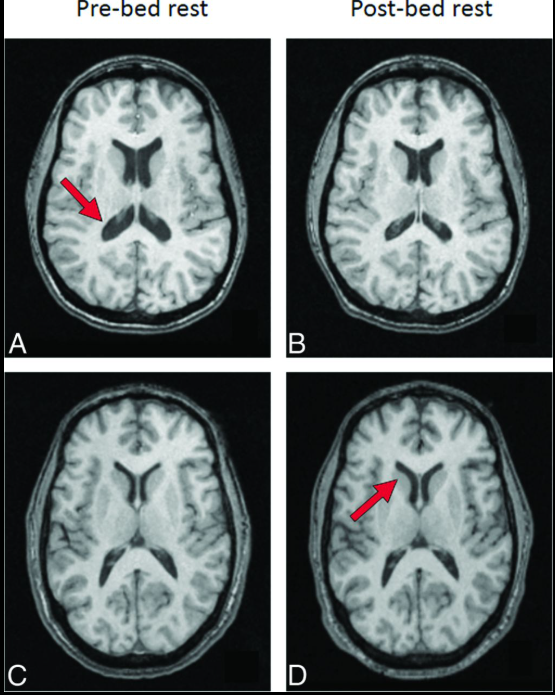

Não bộ của phi hành gia có xu hướng dịch chuyển lên phía trên và ra sau bên trong hộp sọ. (Ảnh: PNAS)

Theo đó, sau thời gian sống và làm việc trên Trạm Không gian Quốc tế (ISS), não bộ của phi hành gia có xu hướng dịch chuyển lên phía trên và ra sau bên trong hộp sọ. Các rãnh não ở vùng đỉnh đầu bị nén lại, trong khi hệ thống khoang chứa dịch não tủy xuất hiện sự thay đổi về hình dạng.

Đáng chú ý, những biến đổi này không đồng đều trên toàn bộ não bộ. Ảnh MRI cho thấy các vùng liên quan đến cảm giác và vận động - những khu vực đóng vai trò quan trọng trong việc giữ thăng bằng và phối hợp cơ thể là nơi chịu ảnh hưởng rõ rệt nhất. Ngoài ra, các nhà khoa học còn ghi nhận những biến dạng cục bộ theo chiều ngang, mang tính phi tuyến và khác nhau giữa phần trên và phần dưới của não.

Kết quả cho thấy não bộ của nhóm người này cũng xuất hiện sự thay đổi về hình dạng và vị trí, khá giống với những gì quan sát được ở phi hành gia. Tuy nhiên, mức độ dịch chuyển lên trên của não không mạnh bằng, và các cấu trúc não nhìn chung vẫn ổn định hơn so với những người thực sự sống trong không gian.

Não bộ của người thường được đặt trong mô phỏng môi trường vi trọng lực mức độ dịch chuyển lên trên của não không mạnh bằng, và các cấu trúc não nhìn chung vẫn ổn định hơn so với những người thực sự sống trong không gian. (Ảnh: AJNR)